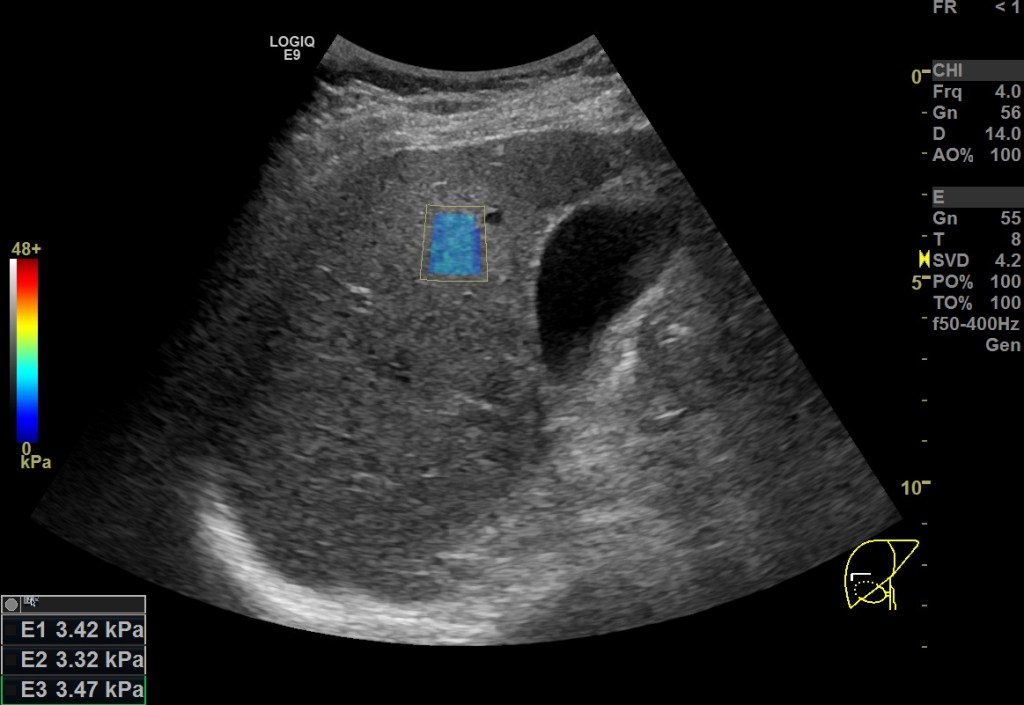

두번째로 생각해볼 점은 거사의 신뢰성을 판단할 때 사분위간 범위를 나누는 것보다 더 직관적인 방법으로서 2D SWE 시행 시 관심영역 내에 색으로 표시되는 부분이 얼마나 균일한 색상으로 고르게 분포되어있는가를 확인하는게 좋은 지표가 될 수 있다는 점입니다. 경험적으로 관심영역 내 색상이 균일한 경우는 여러번 측정했을 때의 측정값 또한 일정하게 편차가 적었습니다(위의 영상 참조).

이러한 경향은 정상환자에서나 간섬유화 등으로 stiffness가 증가한 환자에서나 공히 보이는 경향이었습니다.

2D SWE를 시행하는 동안에는 이렇게 관심영역의 색상균일도를 확인하면서 한 번 측정할 때마다 제대로 측정한 유효검사인지를 쉽게 체크할 수 있었습니다.